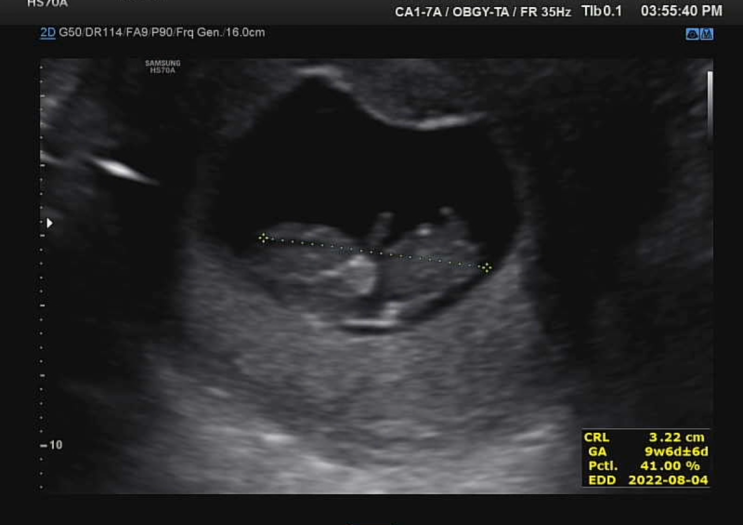

임신 10주차, 하리보 초음파 티도 안나는 배크기

임신할 줄은 꿈도 못꾸고 차근차근 결혼준비 10월로 날을 잡았었쥐 웨딩베뉴 상담하고 온날~ 1월이 우리 결...